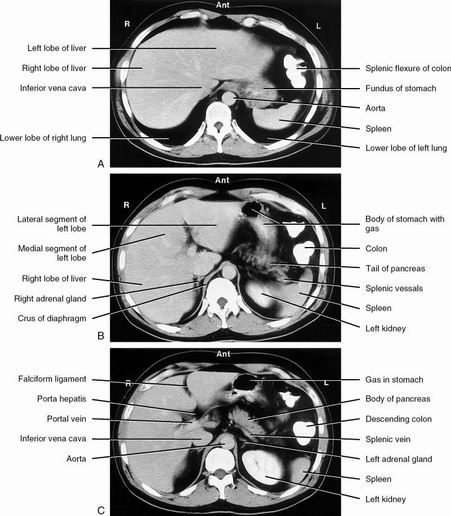

| Arterial phase & portal venous phase | |